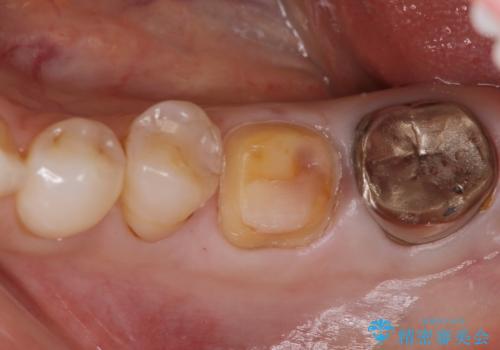

- 他院で、仮歯にしたがセラミックの値段が高すぎると思ったため治療相談も含めて来院された患者様です。

仮歯を新調させていただき、再度虫歯治療を行なって、歯の形を作りセラミックを入れさせていただきました。

フルジルコニアクラウン 7万円(税抜)

仮歯 1万円

にて治療させていただきました。色に関しても喜んでいただき満足されていました。